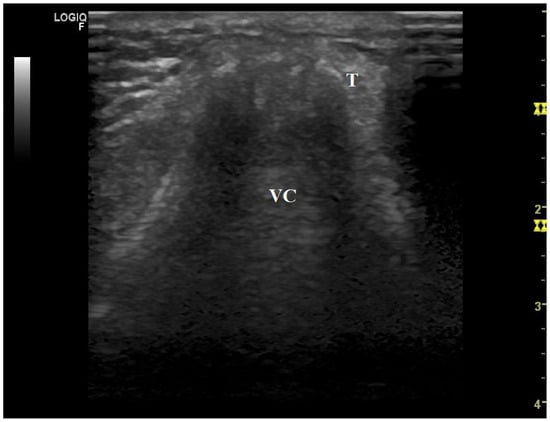

- Brekka, A.K.; Vollsæter, M.; Ntoumenopoulos, G.; Clemm, H.H.; Halvorsen, T.; Røksund, O.D.; Andersen, T.M. Adjustments of non-invasive ventilation and mechanically assisted cough by combining ultrasound imaging of the larynx with transnasal fibre-optic laryngoscopy: A protocol for an experimental study. BMJ Open 2022, 12, e059234. [Google Scholar] [PubMed]

- Andersen, T.; Sandnes, A.; Brekka, A.K.; Hilland, M.; Clemm, H.; Fondenes, O.; Tysnes, O.B.; Heimdal, J.H.; Halvorsen, T.; Vollsæter, M.; et al. Laryngeal response patterns influence the efficacy of mechanical assisted cough in amyotrophic lateral sclerosis. Thorax 2017, 72, 221–229. [Google Scholar] [PubMed]